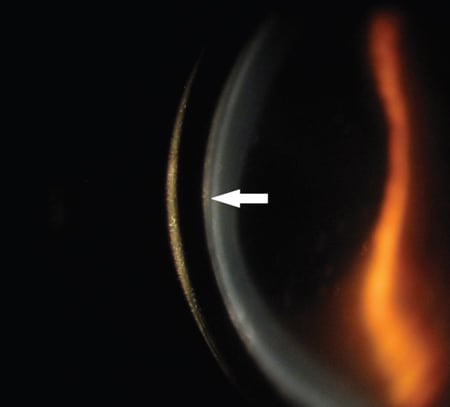

Scleral contact lenses have the distinction of successfully fitting eyes that have irregular corneas when all other design options have failed. In some cases, however, piggybacking a scleral lens onto a soft contact lens (Figure 1) is necessary to improve fit or function. In this column, I describe some typical situations where you may wish to consider this option.

Figure 1. Soft lens sandwiched between a scleral lens and the cornea.